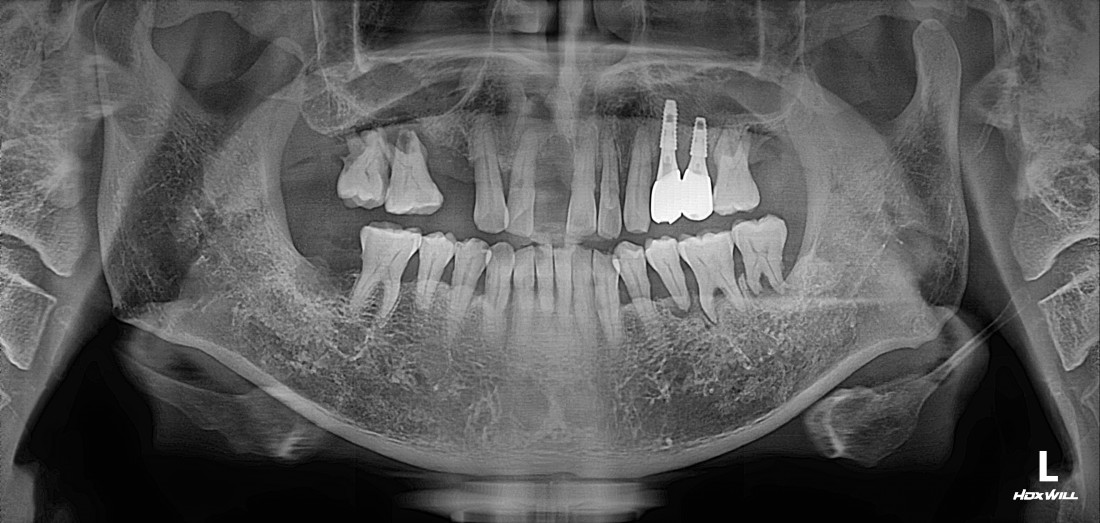

신경쓰이는 앞니 임플란트를

예쁘게 완성하는

광주 앞니임플란트 치과에서

광주 앞니임플란트가 필요할 때

무엇보다도 주변 치아와

잘 어울리고, 잘 씹어지는지가

앞니임플란트 성공의 포인트인데요.

광주 앞니임플란트

구강외과 전문의가

직접 진료하나요?

광주 앞니임플란트치과의

앞니 임플란트 치료원칙 3가지는

1. 안 아프게

2. 예쁘게

3. 잘 씹어지게

입니다.